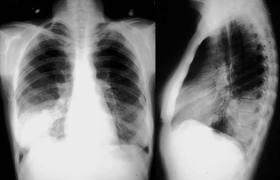

Relación entre los resultados de la radiografía de tórax y el inicio del tratamiento antibiótico en el tratamiento de la neumonía adquirida en la comunidad por médicos generales

04 diciembre 2024

En los pacientes con sospecha de neumonía adquirida en la comunidad (NAC), los médicos de cabecera tuvieron sistemáticamente en cuenta los resultados de las pruebas de respuesta positiva para iniciar el tratamiento antibiótico y tuvieron mucho menos en cuenta las pruebas de respuesta negativa. Estos resultados justifican la aclaración de qué se debe hacer en los casos de sospecha clínica de NAC sin confirmación radiológica. The Annals of Family Medicine, noviembre de 2024,